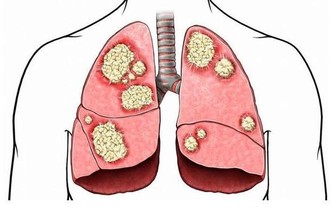

這種思維是告訴我們,抑鬱症其實是一種心理和精神上的異常現象,並非真正意義上的生理問題,而真正意義上的生理問題,我所指的是一些重大疾病,而類似一些亞健康,每個人或多或少都存在一些。

所以,患上抑鬱症,不是什麼絕症、癌症,從這一點上我們的害怕心理負擔,就能卸下來很多很多。